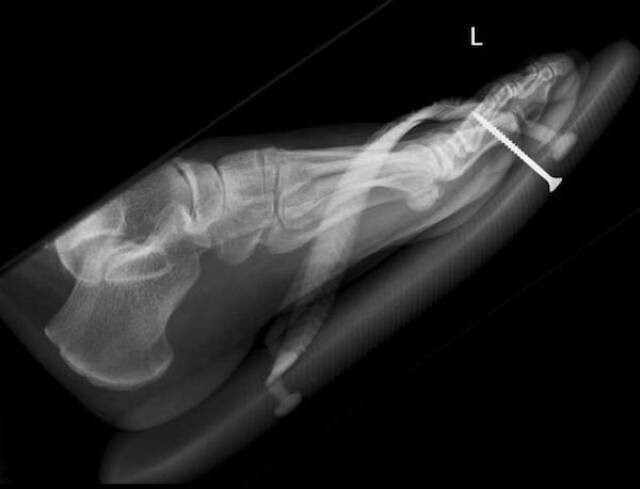

Лікарі-рентгенологи та хірурги за свою багаторічну практику бачать багато чого дивовижного та несподіваного.